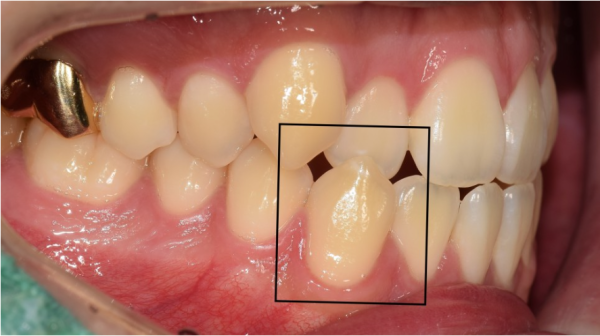

뿐만아니라 이렇게 측면에서 보면 앞니가 앞닿아 있는것 뿐만 아니라

송곳니의 경우에는 아예 아랫니가 윗니 위쪽으로 나와있습니다.

이러한 부정교합을 보이고 있기 때문에 교정을 통해 치료가 필요한 상황입니다.

Not only that, but from the side, it's not only that your front teeth are in front of you

In the case of fangs, the lower teeth are protruded from the upper teeth.

Because of this malocclusion, treatment is needed through correction.